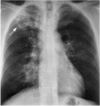

**Lungeødem/stase**: **Huskeregel**: * **Lungeødem** = væske INDEN i lungen * **Pleuraeffusion** = væske UDEN for lungen **Hyppigste årsager**: **1** **Udredning og Diagnose**: 1) **Rtg. thorax**: for at afklare om der er lungeødem eller ej 2) **Ekkokardiografi**: for at afklare om årsagen til lungeødemet (kardiogent eller ikke-kardiogent) **Behandling**: **2**

1: * **Kardiogent lungeødem (hyppigst)**: **fx hjertesvigt (hyppigst)**, etc. * **Ikke-kardiogent lungeødem**: fx pneumoni, sepsis, etc. 2: 1) - Iltbehandling - **Furix** - **Nitroglycerin** 2) Evt. CPAP/NIV ved respirationssvigt 3) Behanlde udløsende årsag **Huskeregel**: - Væske i lunger (**Lungeødem**) --> driv den væk (diuretika + nitrat) - Væske i pleura (**Pleuraeffusion**) --> tap den